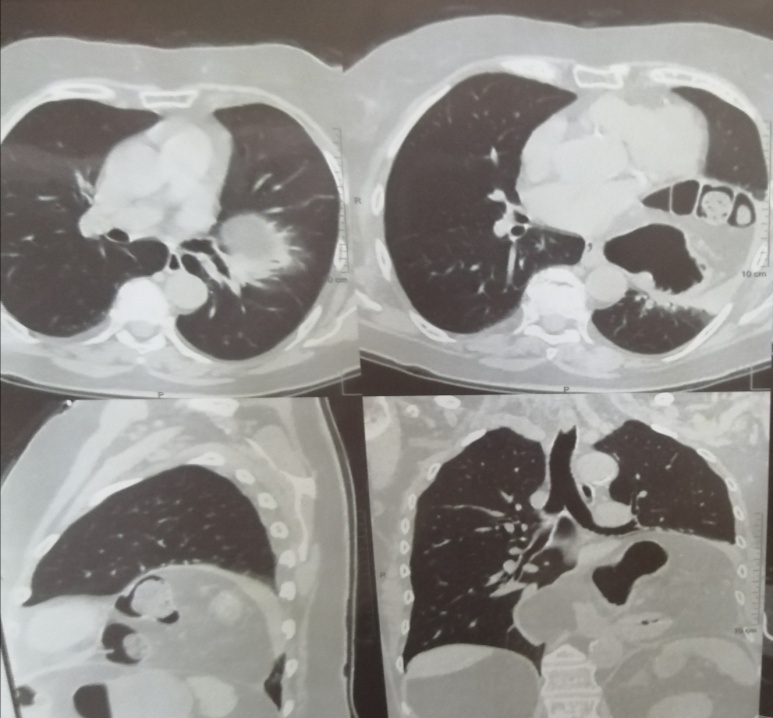

Рис. 5. КТ-признаки гигантской грыжи пищеводного отверстия диафрагмы

Компьютерная томография органов грудной клетки, органов брюшной полости от 02.01.2020 г. (рис. 5): гигантская грыжа пищеводного отверстия диафрагмы с наличием компрессионных изменений в прилегающей легочной ткани; жидкость в полости перекарда; коронаросклероз; деформация желчного пузыря; повышение плотностных показателей желчи; КТ-картина образования обоих надпочечников; кистозное образование в синусе левой почки — парапельвикальная киста; дивертикулез нисходящей ободочной и сигмовидной кишки; формирующаяся пупочная грыжа; атеросклероз аорты и ее ветвей; антелистез L4 позвонка; неполная правосторонняя сакрализация L5.